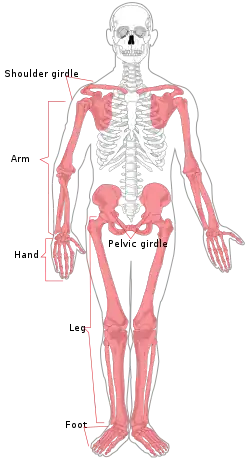

| Appendicular skeleton | |

Human appendicular skeleton | |

The appendicular skeleton is the portion of the skeleton of vertebrates consisting of the bones that support the appendages. There are 126 bones. The appendicular skeleton includes the skeletal elements within the limbs, as well as supporting shoulder girdle and pelvic girdle.[1] The word appendicular is the adjective of the noun appendage, which itself means a part that is joined to something larger.

The appendicular skeleton is divided into six major regions:

- Shoulder girdle (4 bones) - Left and right clavicle (2) and scapula (2).

- Arms and forearms (6 bones) - Left and right humerus (2) (arm), ulna (2) and radius (2) (forearm).

- Hands (54 bones) - Left and right carpals (16) (wrist), metacarpals (10), proximal phalanges (10), intermediate phalanges (8) and distal phalanges (10).

- Pelvis (2 bones) - left hip bone and right hip bone (2).

- Thighs and legs (8 bones) - Left and right femur (2) (thigh), patella (2) (knee), tibia (2) and fibula (2) (leg).

- Feet and ankles (52 bones) - Left and right tarsals (14) (ankle), metatarsals (10), proximal phalanges(10), intermediate phalanges (8) and distal phalanges (10).